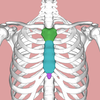

25

xiphoid process

26

xiphoid prcoess

27

manubrium

28

manubrium

29

sternum

30

sternum

31

costal cartilegde

32

costal cartledeg (front inneer ribs)